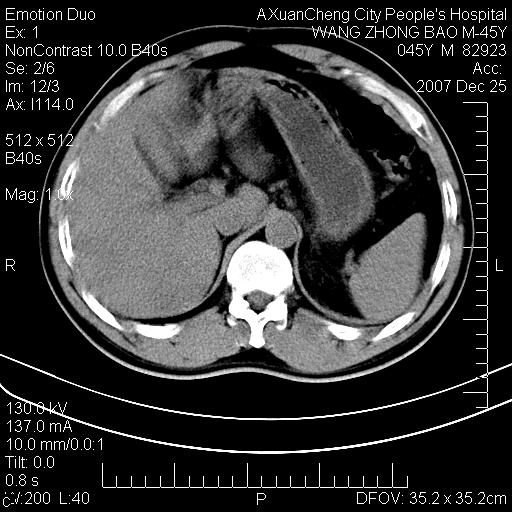

以下是引用qiuleiyu在2007-12-25 18:14:00的发言:[br]胰腺增大,周边渗出改变,肾前筋膜明显增厚,示少量积液.胆囊壁毛糙,周边少许渗出,胆总管壁厚,异常强化,然扩张不明显.结合病程急短;考虑;胆管炎,胆囊炎,胆源性胰腺炎可能大,请结合实验室检查及随访.

以下是引用lisihao在2007-12-25 14:23:00的发言:[br]急性水肿型胰腺炎[br]依据:1、胰腺弥漫性肿大,边缘稍毛糙;[br] 2、双侧肾周筋膜增厚,尤以左侧为甚(重要征象)[br] 3、双侧后胸膜增厚(刺激性炎症);[br] 4、结合病史,查血尿淀粉酶应该可以确诊。